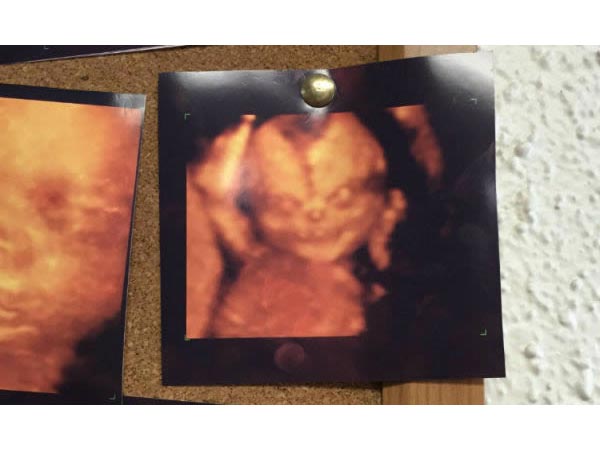

భయంకరమైన ఫేస్

వీక్లీ చెకప్ కి వెళ్లినప్పుడు ఆల్ట్రాసౌండ్ స్కాన్ లో భయంకరంగా, ఎర్రగా కనిపిస్తున్న ఈ ఇమేజ్ చూసి.. తల్లిదండ్రులు భయపడ్డారు. ఇది 4డీ ఆల్ట్రాసౌండ్ స్కాన్.

ఎవిల్

ఇంకా పొట్టలో ఉన్న బేబీ స్టార్ వార్స్ సినిమాలో ఎవిల్ ఎంపిరర్ ఉన్నట్టు ఉంది కదా. ఇది చూసిన తల్లి వెంటనే రెండింటినీ కంపేర్ చేసింది. స్కాన్ రూంలో ఉన్నవాళ్లంతా పొట్టచెక్కలయ్యేలా నవ్వేశారు.